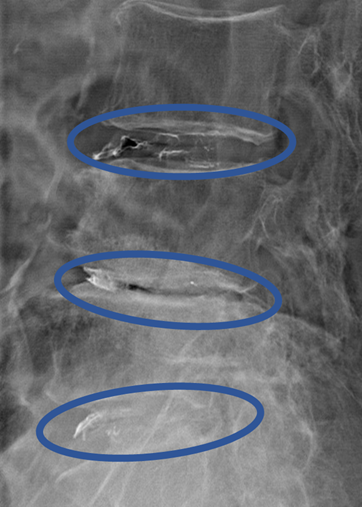

DiscoGelを入れた後の画像になります。

治療は 30分 程度で終了

回復室で休憩後、歩いて帰院されました。